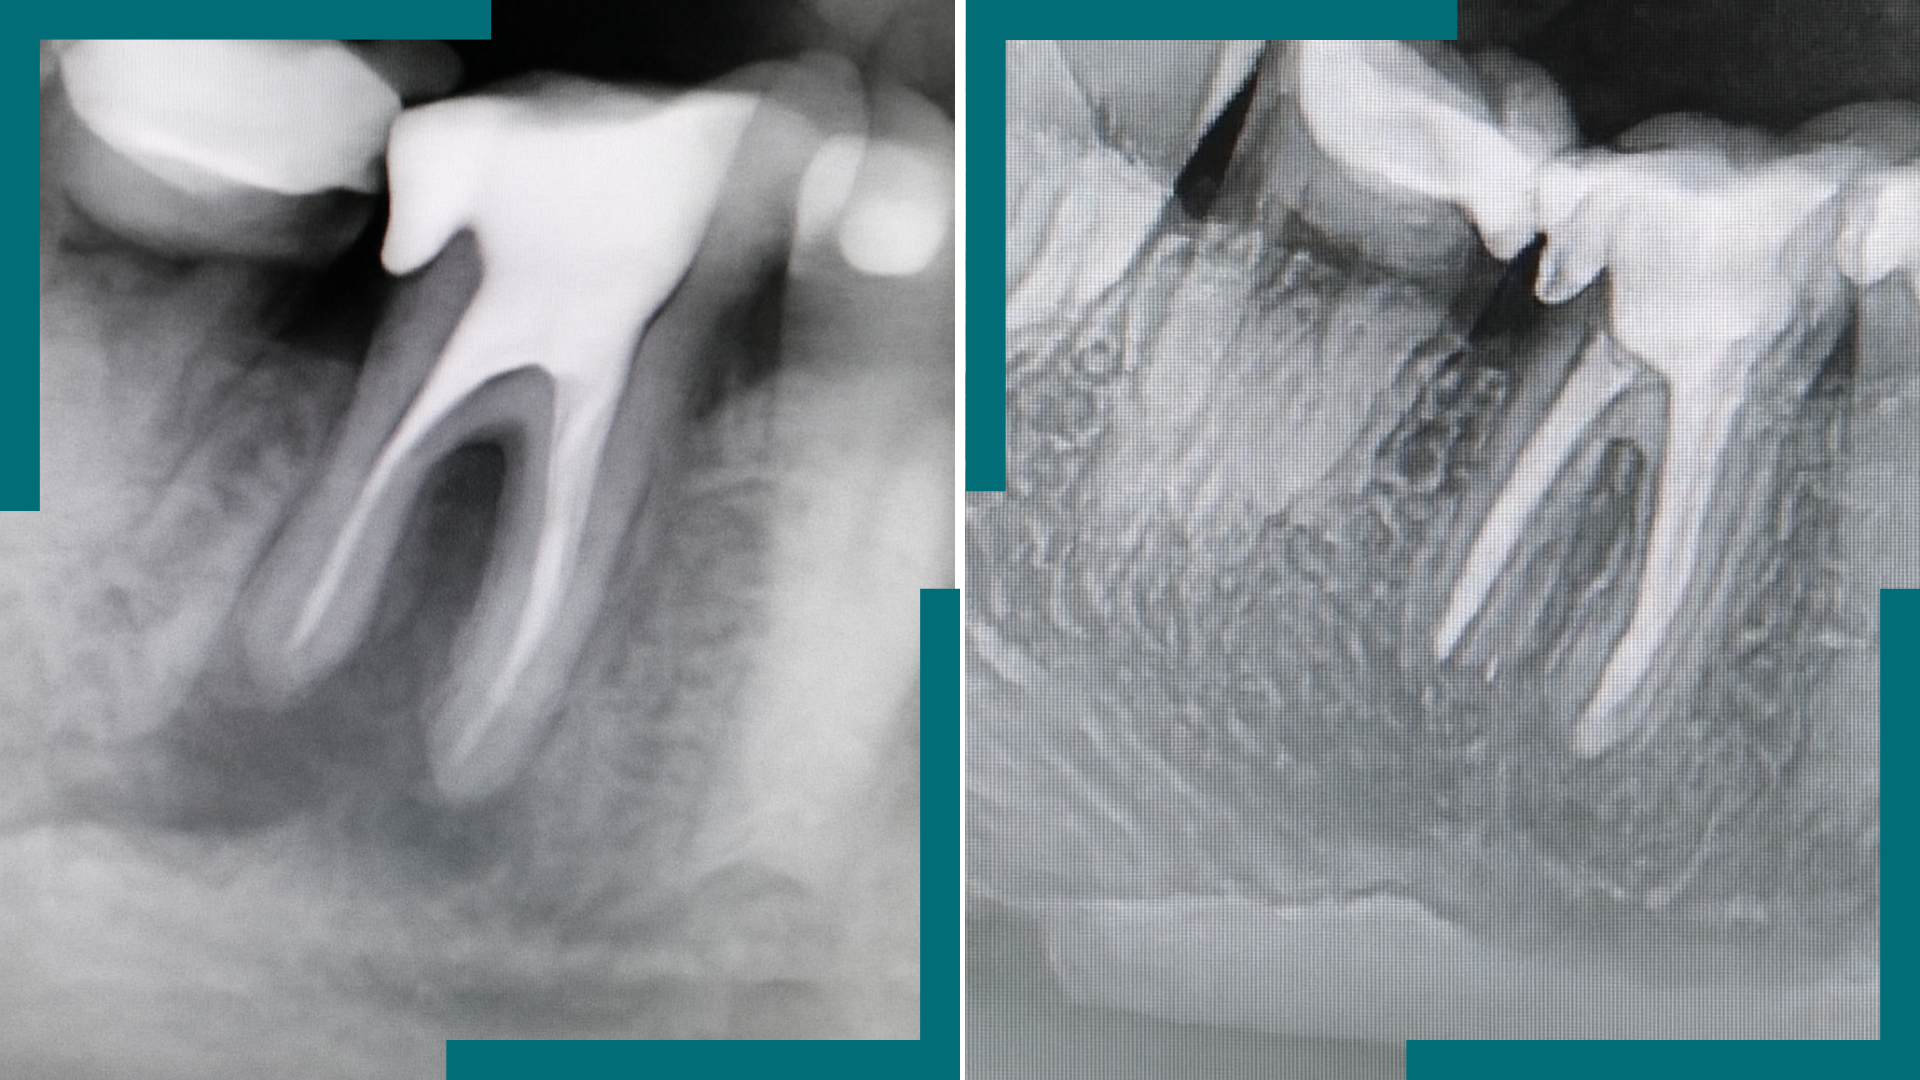

- Répondez aux questions concernant l'image.